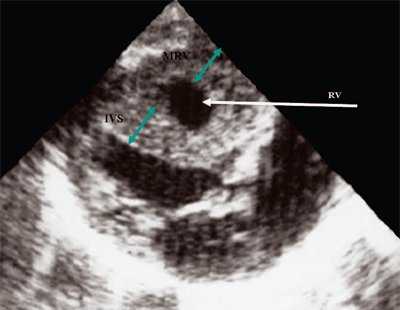

Для левого желудочка признаком объемной перегрузки являются увеличение полости левого предсердия и желудочка, а также экскурсии межжелудочковой перегородки и миокарда задней стенки левого желудочка (рис. 4).

Рис. 4. Объемная перегрузка левых отделов сердца. В- и М-сканирование. Отмечается усиление экскурсии межжелудочковой перегородки и миокарда задней стенки левого желудочка.

IVS - межжелудочковая перегородка, MLV - миокард левого желудочка, LV и RV - левый и правый желудочек.